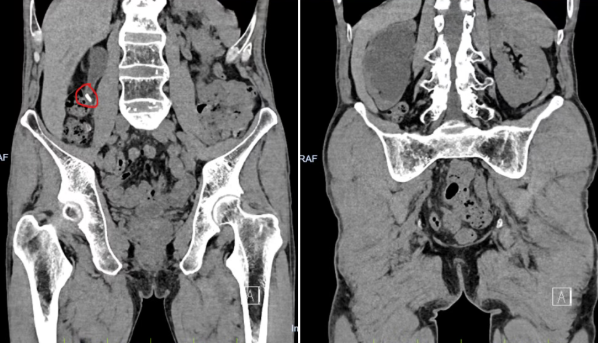

半年前,孙先生开始出现右侧腰背部疼痛,每次发作持续约半小时。由于没有尿频、尿急、尿痛等症状,他便自行在家服用排石药物。然而,病情并未好转。一个月前,孙先生来到长春国文医院就诊,经泌尿系CT检查发现,导致他长期疼痛的“元凶”竟是右侧输尿管上段的一颗结石。

此时,结石已导致上段输尿管及肾盂积水,甚至出现右侧肾皮质变薄的迹象,意味着肾脏已因长期堵塞出现功能性损伤。